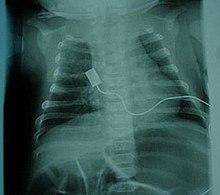

X-ray showing bell-shaped torso due to atrophy of intercostal muscles and using abdominal muscles to breathe. Bell-shaped torso is not specific to individuals with SMA

• Bell-shaped torso (caused by using only abdominal muscles for respiration) in severe SMA type